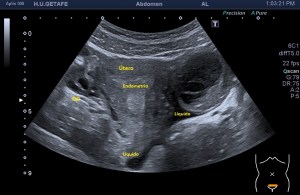

Bien, hemos visto una lesión que es un quiste hidatídico calcificado, pero te preguntarás, si nunca viste uno, ¿cómo es uno cuando tiene «hijas»?, es decir, cuando está activo…Mira este corte transversal de un hígado:

La LOE es de aspecto redondeado, heterogéneo, con multitud de pequeñas imágenes anecoicas e hipoecogénicas, de diferentes tamaños. Esta lesión fue estudiada también mediante otra técnica de imagen, la RMN donde se observa una imagen hiperdensa, con una amalgama de lesiones bordeando a periferia de la misma, de distintos tamaños como se objetiva en la imagen del mismo paciente, de la ecografía inmediatamente superior (Imagen 7). La lesión es activa, por tanto debió de ser tratada, la patología es potencialmente mortal en caso de que el quiste se rompiese.